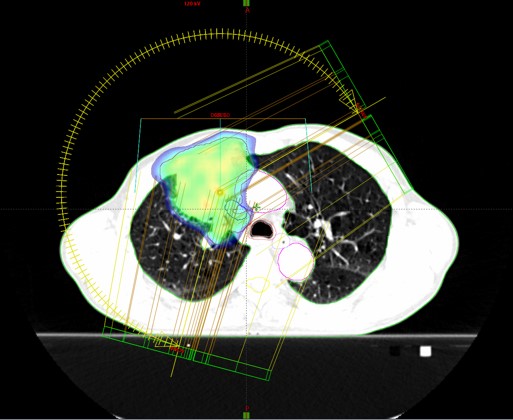

Bolesnik, rođen 1954.

Ca planocellulare bronchi lobi superioris pulmonis lateris dextri cum lymphadenopathia mediastinalis (PD-L1 2%) (2019.)

SBRT tm prim. et meta mediastini (12./2019.)

SABR meta pulmonis (12.12.2022.)

Rezultat – 36 mjeseci nakon RK

smanjenje tumora pluća za 85.9 %